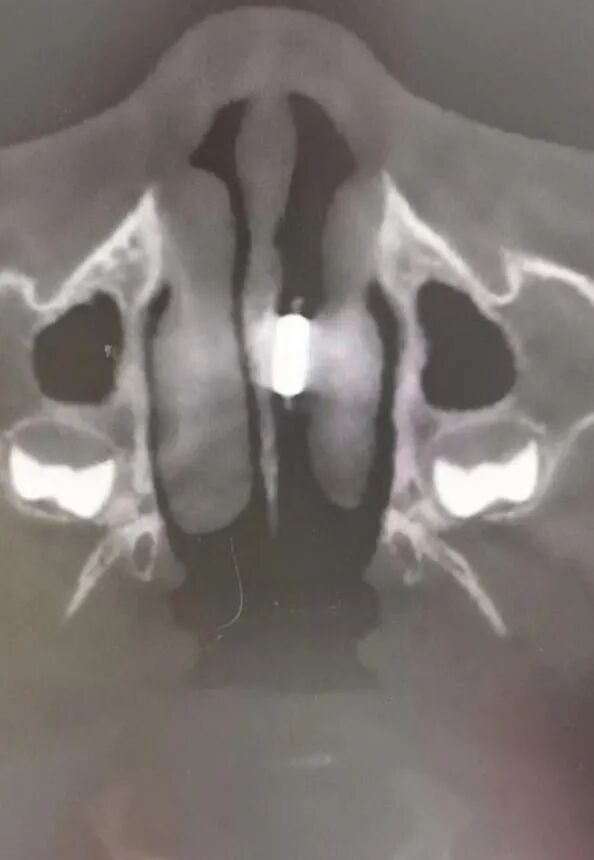

医生建议家长带着孩子再去拍CT检查,由于孩子年纪太小,难以配合CT检查。在与家长充分沟通之后,选择了镇静下卧式口腔CBCT。

“CT结果显示,孩子的鼻腔内有金属异物!”

医生立即将孩子转诊到综合医院。据悉,当晚就给孩子做了全麻手术,异物被取出后大家才发现,原来那是一颗围棋子。

“罪魁祸首”围棋子